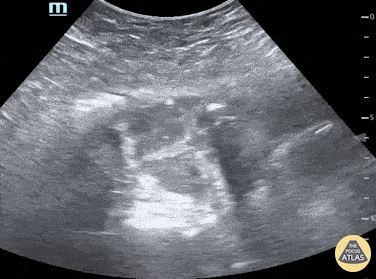

Small bowel obstruction (SBO) featuring “to and fro” movement and tanga sign. Francisco Norman